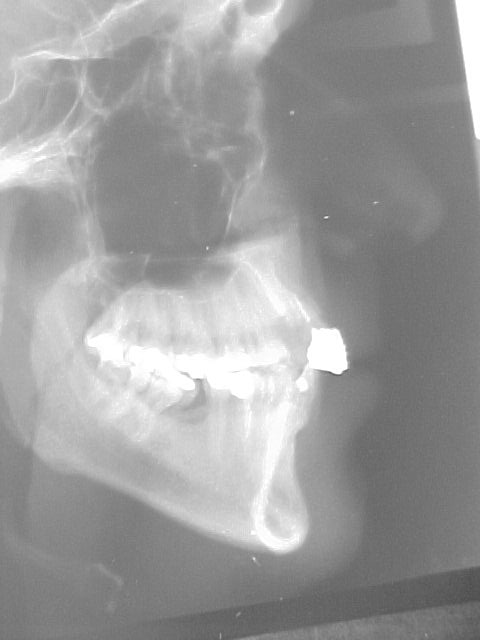

Preparação para instalação do "aparelho ortodôntico" (canino reconstruído em resina rápida autopolimerizável, retida por fio metálico sobre raiz residual)

Início do tratamento ortodôntico. Com a extrusão do canino estaremos induzindo ao nivelamento ósseo para a instalação de implante nesse local.